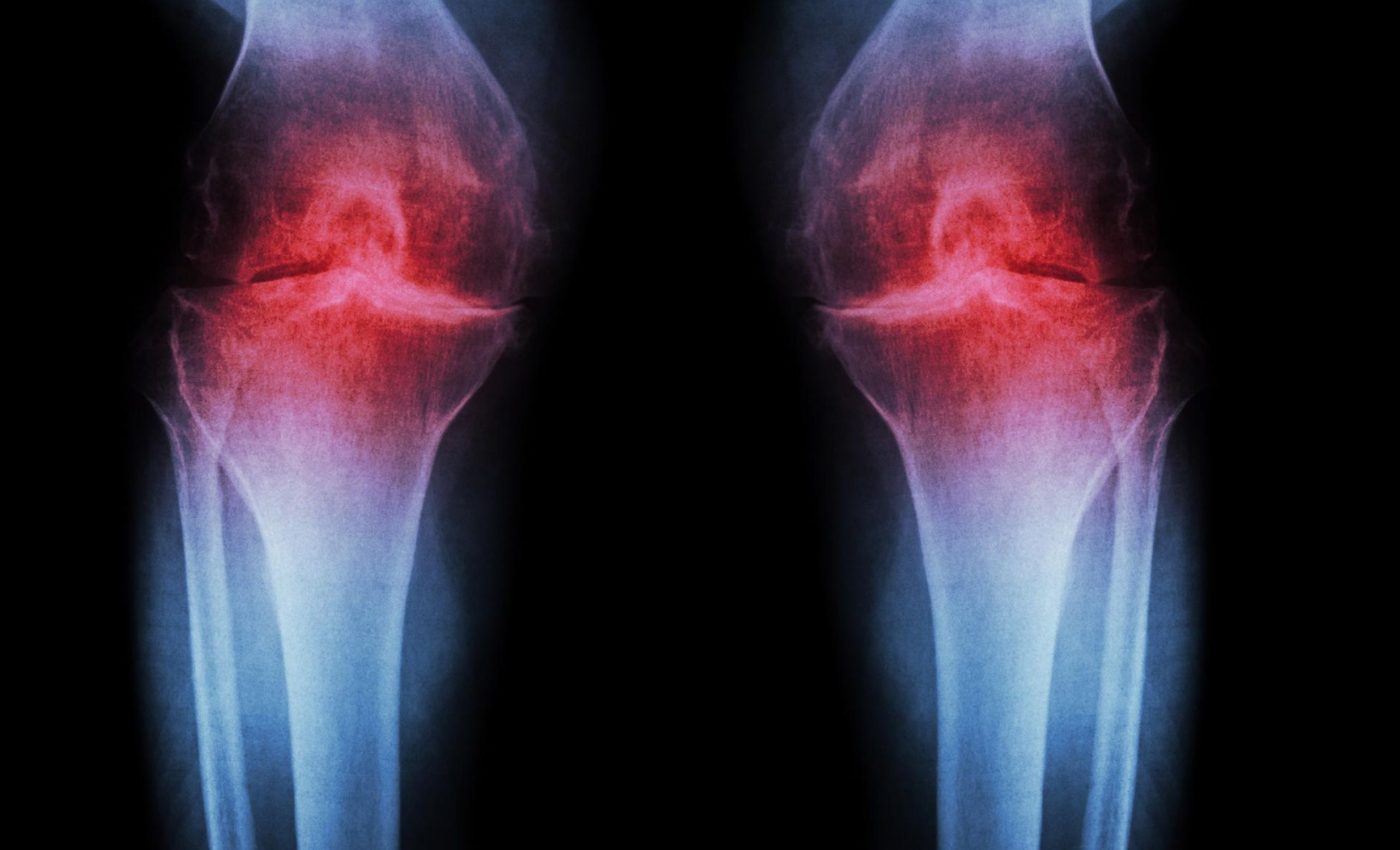

La osteoartritis es una de las enfermedades articulares más comunes y debilitantes del mundo. Afecta a millones de personas y, hasta ahora, no tiene cura. Sin embargo, una nueva investigación sugiere que un tratamiento experimental podría cambiar radicalmente este panorama en el futuro cercano.

Este avance es especialmente relevante si se considera que la osteoartritis progresa en varias etapas, desde un desgaste leve hasta la pérdida total de cartílago, donde el hueso queda expuesto y el dolor se intensifica. Actualmente, en fases avanzadas, las opciones suelen limitarse a cirugías invasivas como el reemplazo articular.